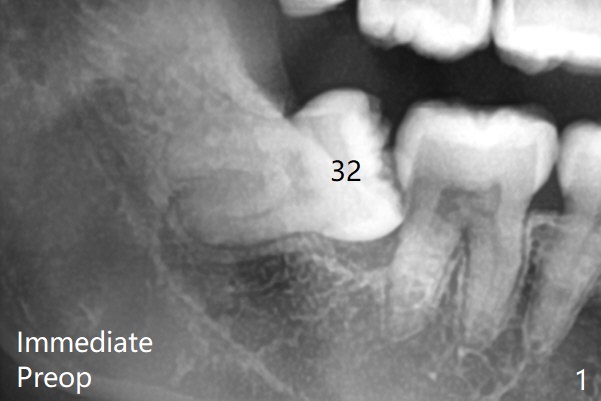

Note bony defects associated with the distal roots of the 2nd molars (red dashed line).